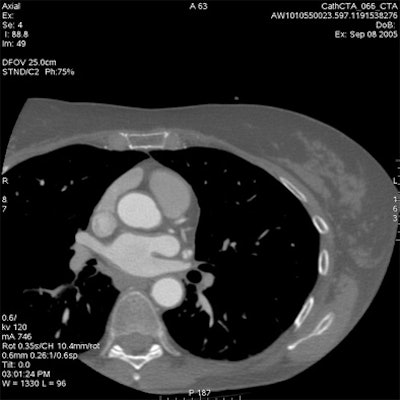

Which image would you rather be responsible for? Small 13-cm FOV (above) provides the best cardiac image quality at the lowest radiation dose compared with medium 25-cm FOV coronary CTA image (below). Thoracic image (bottom) maximizes anatomic coverage but at the cost of additional radiation and potentially more incidental findings. All images courtesy of Dr. Matthew Budoff.

The heart fits in a 25-cm field-of-view, permitting the use of a small bowtie filter in medium-sized and sometimes even larger patients, Budoff said. "We're only worried about the heart," he said.

For example, using protocol parameters of 600 mA, 120 kV, and a heart rate of 60 bpm, a small cardiac bowtie filter (standard 25-cm FOV) permits cardiac images to be acquired at dose-length product (DLP) of 474 (8.0 mSv), Budoff said. A medium bowtie filter (allowing reconstruction to 36-cm FOV) affords a dose of 791.4 DLP (13.4 mSv).

From there, expanding the FOV to the entire thorax for screening of other important findings (lung, breast, axilla, mediastinum, and spine) would actually boost the radiation dose by 67.5%, he said.